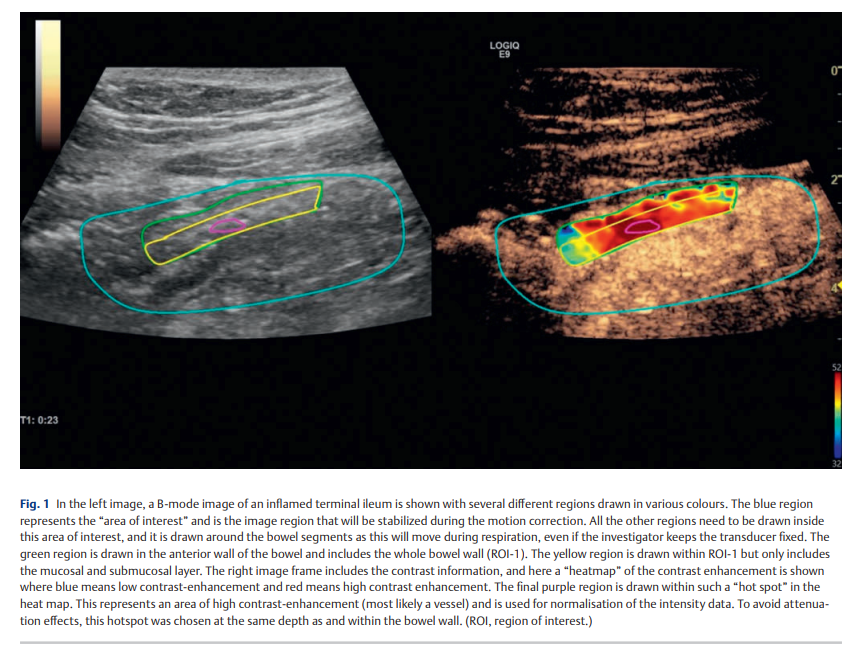

我们前瞻性研究了 2015 年至 2019 年间接受结肠镜检查和 Sonazoid 动态对比增强超声的 48 例克罗恩病患者。我们将最严重病变区域的局部简化克罗恩病内镜评分与 Vuebox 获得的参数进行比较,这些参数包括峰值增强、曲线下流入和流出面积、流入和流出速率以及流入灌注指数。感兴趣区 1(ROI-1)包含肠壁全层,感兴趣区 2(ROI-2)包含黏膜和黏膜下层。使用线性数据和标准化数据。技术失败或拟合优度值 <80% 视为检查失败。